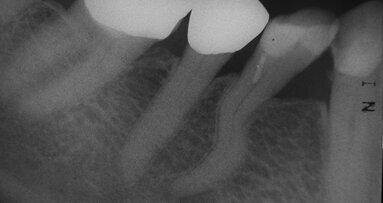

_Une patiente âgée de 81 ans s’est présentée avec une douleur typiquement causée par une pulpite dans le secteur ...